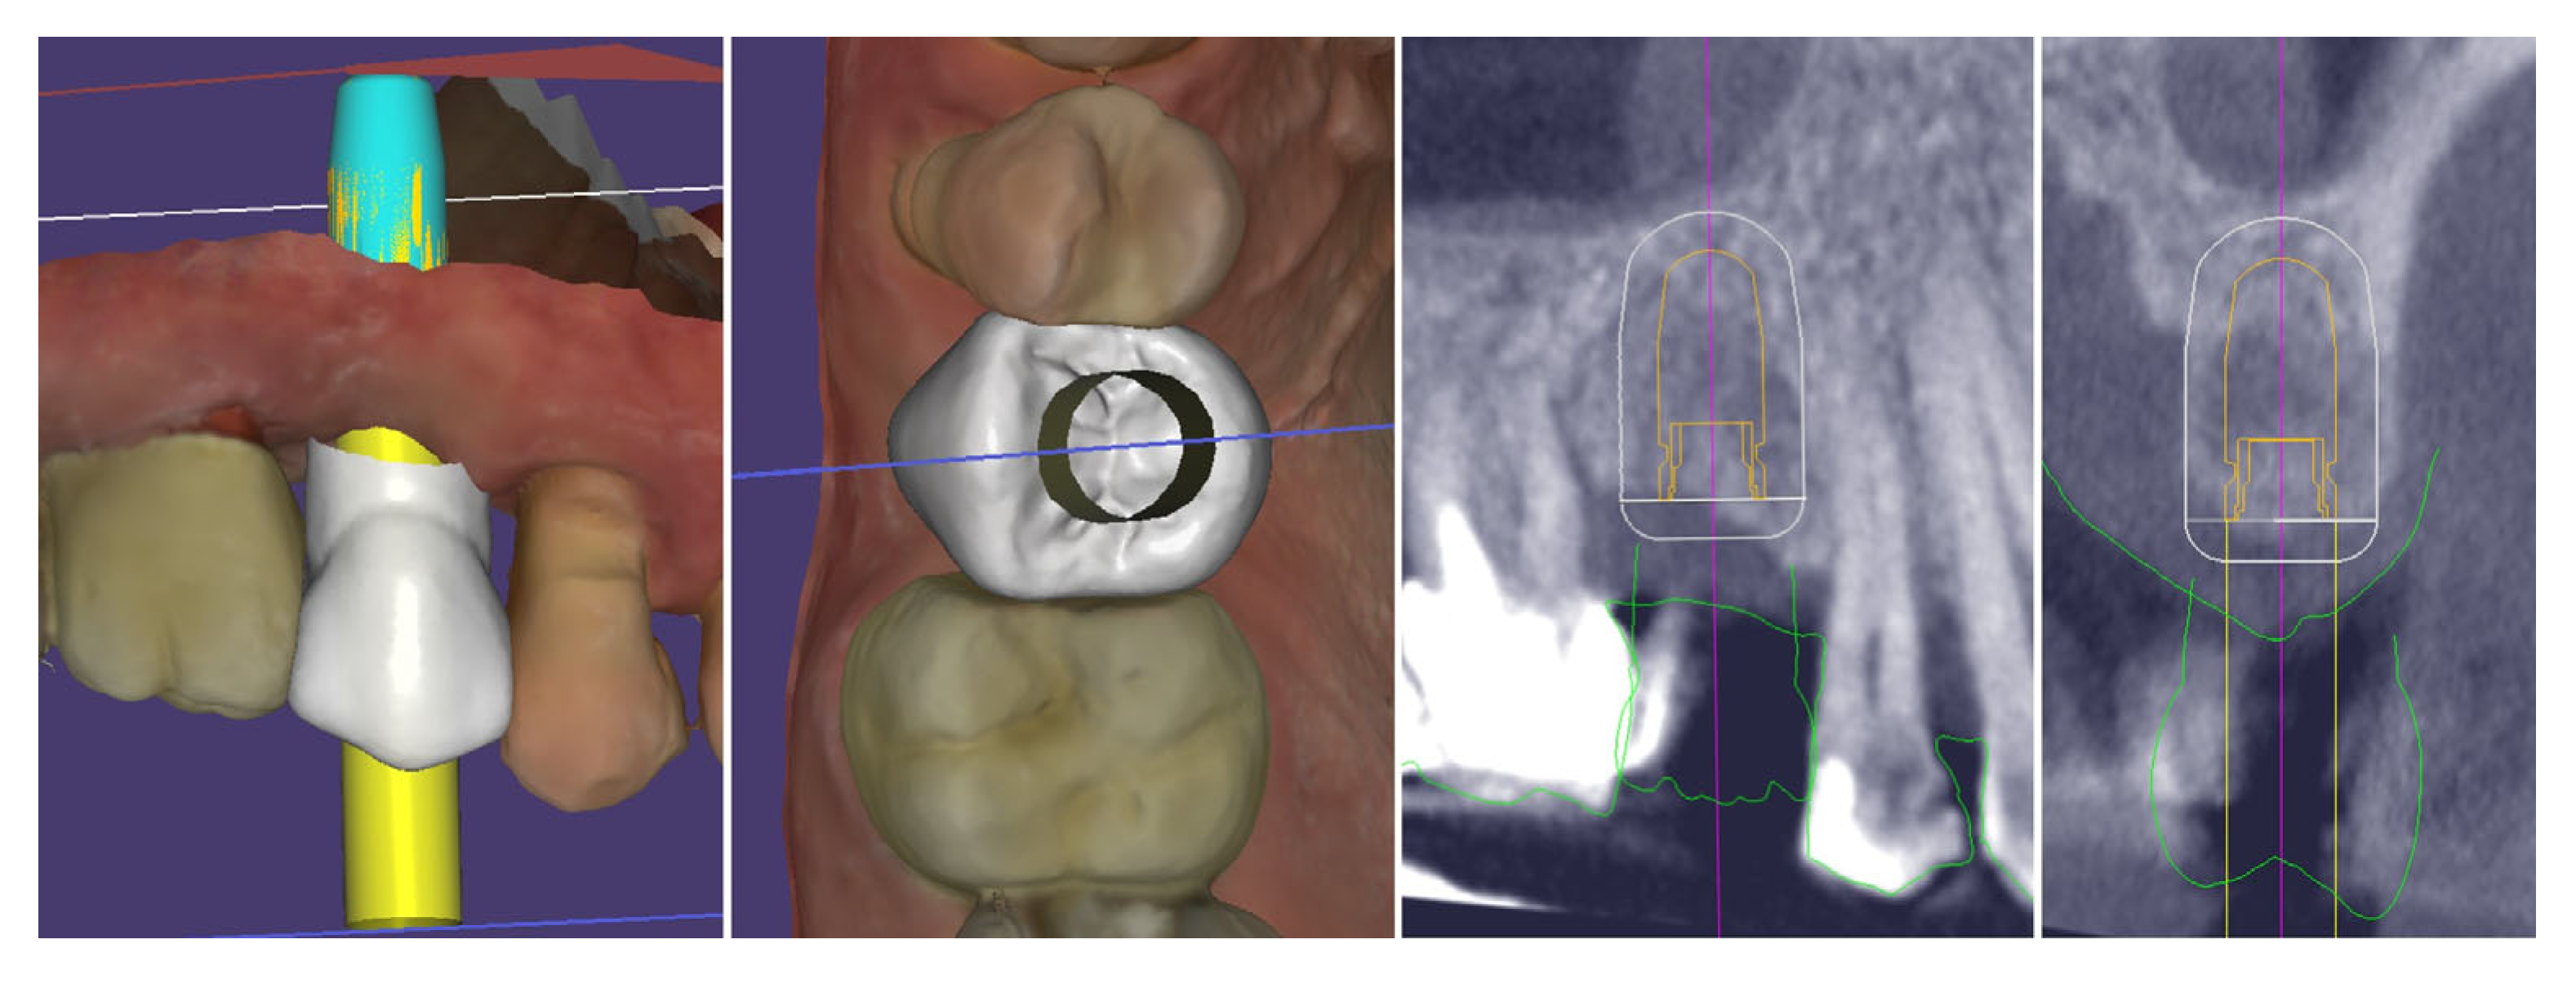

2. Materials and Methods—Clinical Case

| Timepoint | Horizontal Thickness (mm) | Vertical Thickness (mm) | Clinical/Radiographic Findings | |

|---|---|---|---|---|

| 1 | Baseline (Day 0) | 2.3 | 2.4 | Initial thin buccal tissue |

| 2 | 2 weeks post-op | Uneventful healing, stable mucosal margin | ||

| 3 | 3 months post-op (with provisional) | 3.4 | 3.4 | Increased thickness, stable bone and mucosa |

| 4 | 4 months post-provisional | 3.5 | 3.6 | Stable peri-implant mucosa around provisional crown |

| 5 | 8 months post-op (final crown) | 3.5 | 4.1 | Final crown placed, harmonious soft tissue contours, and stable crestal bone |

| 6 | 14 months post-definitive | Long-term stability of soft tissue and crestal bone confirmed |